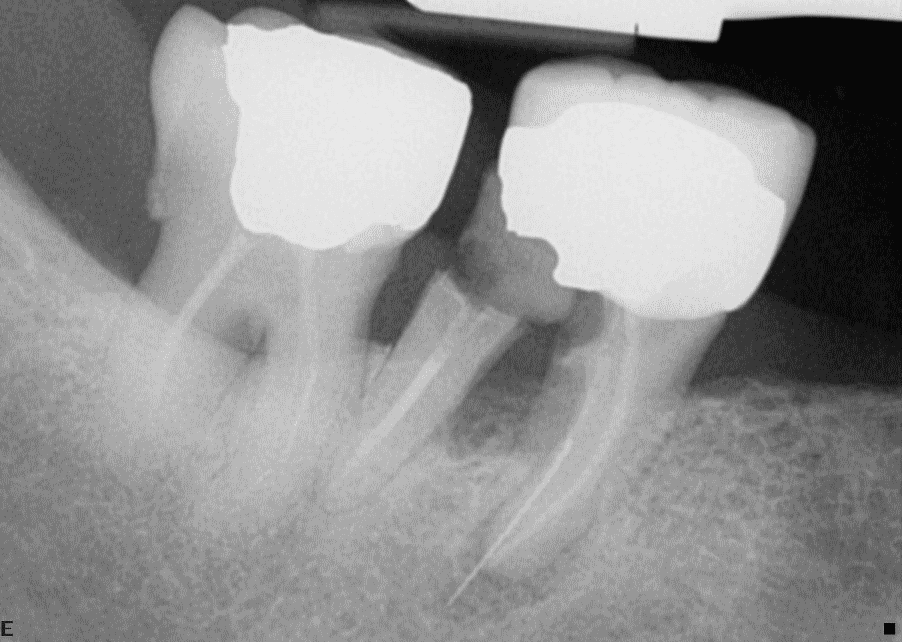

Tooth 47 is affected by periodontitis extending into the furcation, is heavily restored and has an inadequate root filling. Tooth 46 has Stage III periodontitis with a Grade III furcation lesion, extensive caries beneath a full coverage crown and a mesial periapical radiolucency. Tooth 46 is unsaveable due to the multiple problems and the extent of caries and periodontitis when considered together. However, despite its compromised prognosis, tooth 47 may be useful tooth to retain following periodontal and endodontic treatment if there is a need or a desire to avoid a free end saddle situation or to provide distal occlusal support.